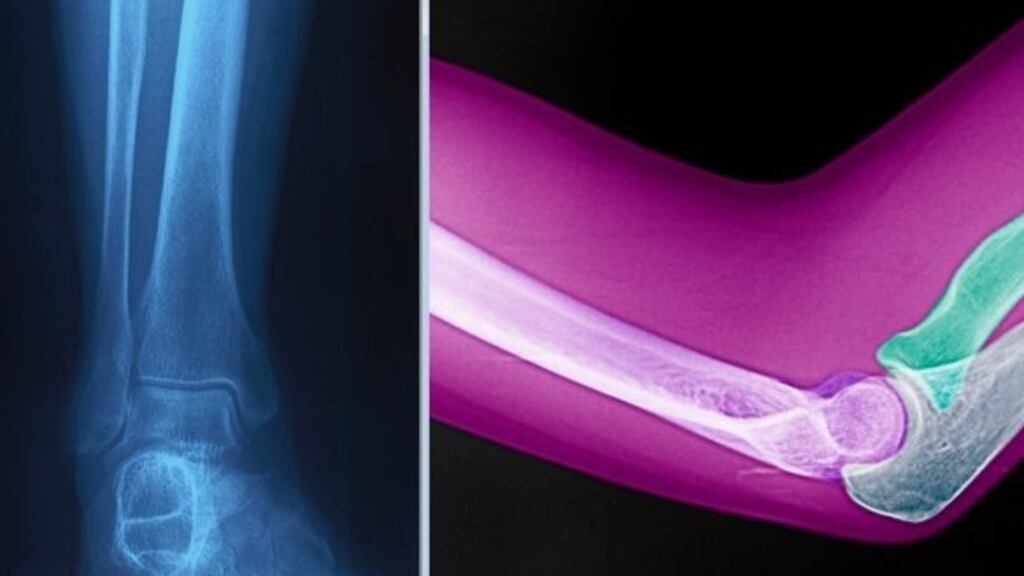

Consultant Odhran Murray, who worked with Dr Hassan in Galway, previously told the inquiry of an instance in which the doctor mistook an X-ray of an ankle for an image of an elbow during a training session with colleagues.